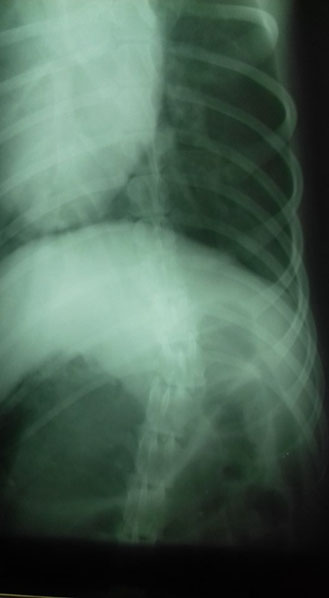

Miglena Dzhurova fand Anfang März 2018 einen verletzten Hund und brachte ihn sofort in die Klinik. Er war von einem Auto angefahren worden. Die Röntgenaufnahmen zeigten leider, dass seine Wirbelsäule gebrochen war - genau an derselben Stelle wie bei Dea aus unserem SOS-Tierschutzprojekt 48.

Dea wurde vor 15 Monaten aus einem Garten gerettet, wo sie mehrere Wochen ohne tierärztliche Versorgung ausgeharrt hatte. Auch bei Dea ergaben damals die Tests, dass sie kein Gefühl mehr in den

Hinterbeinen hatte, auch nicht in tieferen Regionen. Wie Dea kann der Rüde seine Körperfunktionen nicht mehr kontrollieren und wird Windeln tragen müssen… auch er ist jung, ungefähr ein Jahr alt

und hat sein Leben eigentlich noch vor sich.

Und auch bei ihm wird eine Operation keine Besserung erzielen.

Gott sei Dank ist der Bruch seiner Wirbelsäule nicht wie bei Dea verschoben, so dass Hoffnung besteht, dass er seine Hinterläufe wird wieder ein wenig einsetzen können. Dies gelang bereits bei